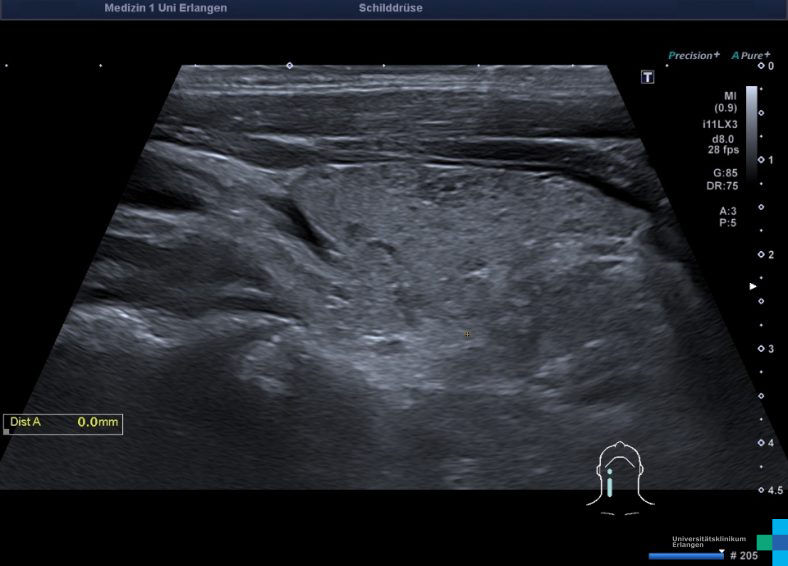

SDD_AIT_XXX_1200.jpg